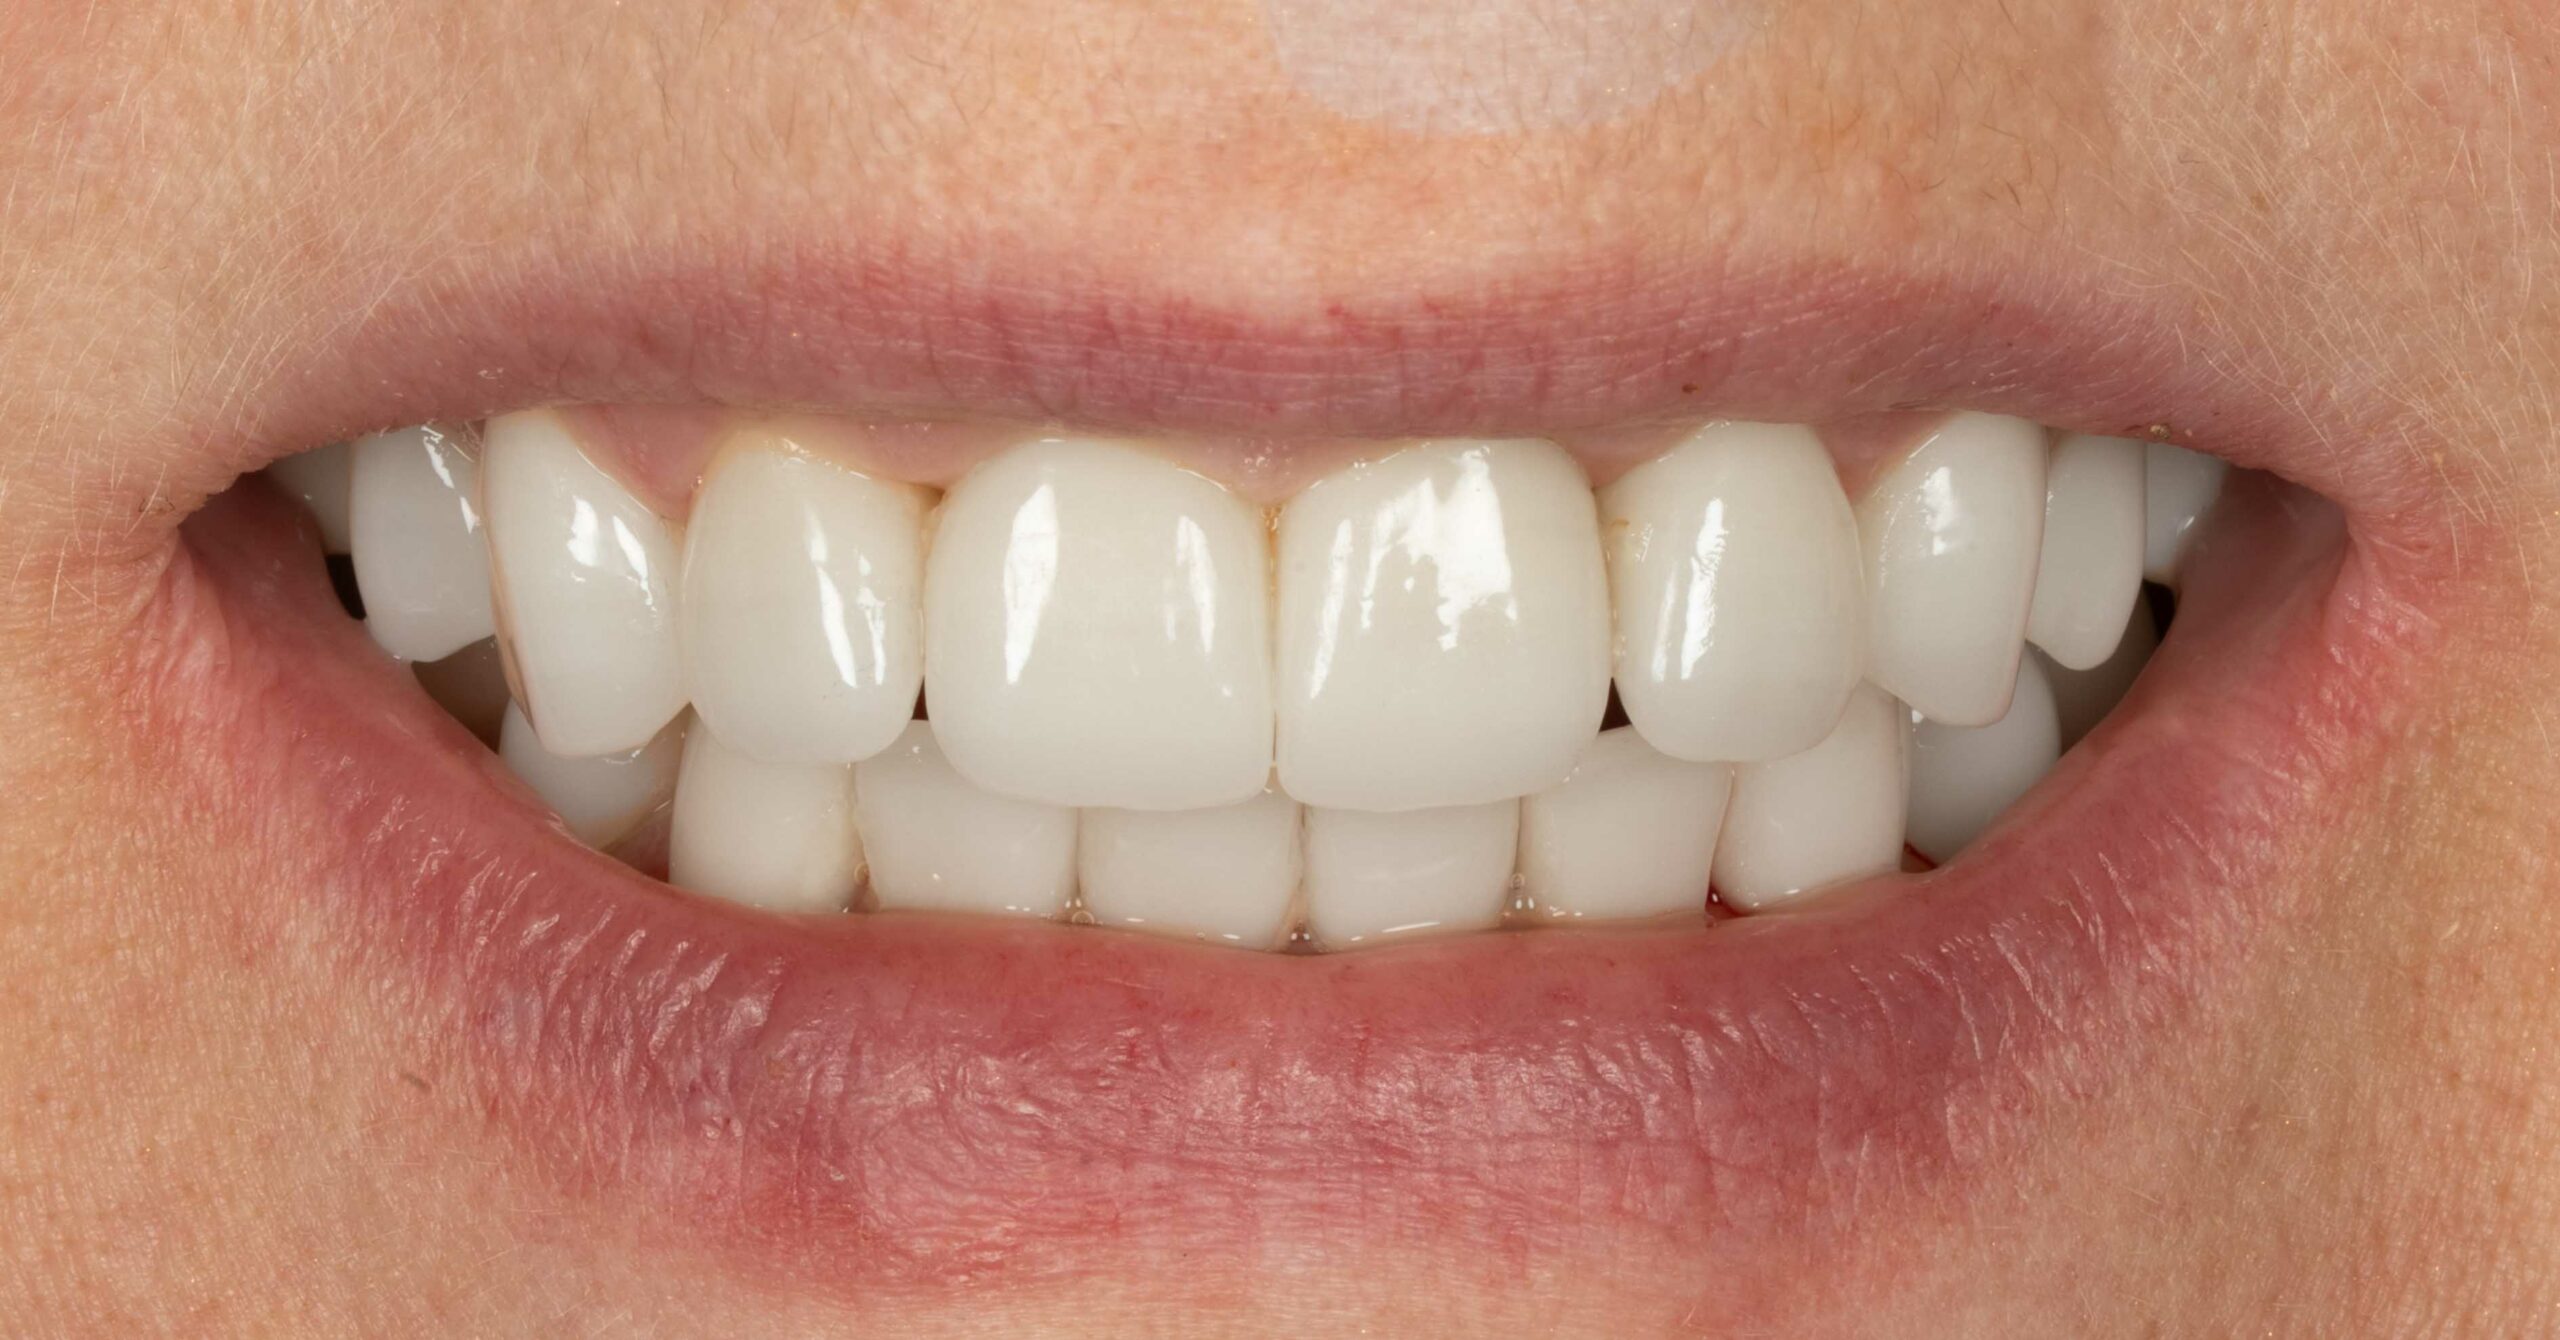

Pacjent zgłosił się z powodu licznych problemów z zębami oraz dolegliwości bólowych głowy. Zęby z powodu znacznej ruchomości nie stanowiły odpowiedniej podpory podczas żucia. Niestety wieloletniej terapia periodontologiczna choroby przyzębia nie przynosiła efektów. Zęby zostały zakwalifikowane do usunięcia. Nowy zgryz został odtworzony i oparty na 6 implantach w szczęce oraz 5 w żuchwie. Informacje z badania stawowe "kondylografii" pomogły zaplanować nowe prawidłowe zwarcie. Poza wyleczeniem dolegliwośći bólowych głowy oraz przywróceniu komfortu żucia i uśmiechu, Pacjent po zakończonej terapii zgłasza znaczne ograniczenie chrapania.

leczenie zaplanował oraz przeprowadził lek. dent Kamil Kikowicz